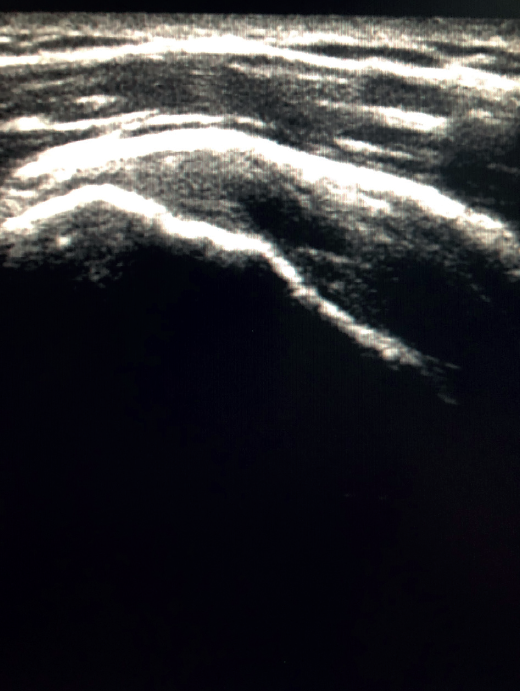

The characteristic ultrasound image of tendinosis consists of local or diffuse thickening accompanied by a hypoechogenic and heterogeneous appearance of the tendon (Figure 3). A fine hypoechoic line over 2 mm in thickness between the tendon of the supraspinatus and the subdeltoid adipose tissue corresponds to subacromial-subdeltoid bursitis, and the presence of fluid in the bursa is related to a high probability of partial or complete injury of the tendon of the supraspinatus muscle(26). In order to achieve greater diagnostic accuracy and distinguish between an inflammatory process and a normal small amount of fluid in the bursa, we should take into account that bursitis, tenosynovitis and tendinitis are characterized by the presence of hyperechoic zones with areas of enhanced flow in the Doppler ultrasound study. Both bursal and articular partial ruptures appear as a hypoechoic discontinuity in the tendon that does not vary on modifying the inclination of the ultrasound probe in either the long axis of the tendon nor its short axis(19). This latter aspect is important in order not to confuse partial lesions with anisotropic phenomena, which are a change in tissue behaviour according to the ultrasound angle of incidence(27)(Figure 4).

Figure 4. Anisotropy at the insertion of the tendon of the supraspinatus muscle. Not to be confused with partial thickness injury.